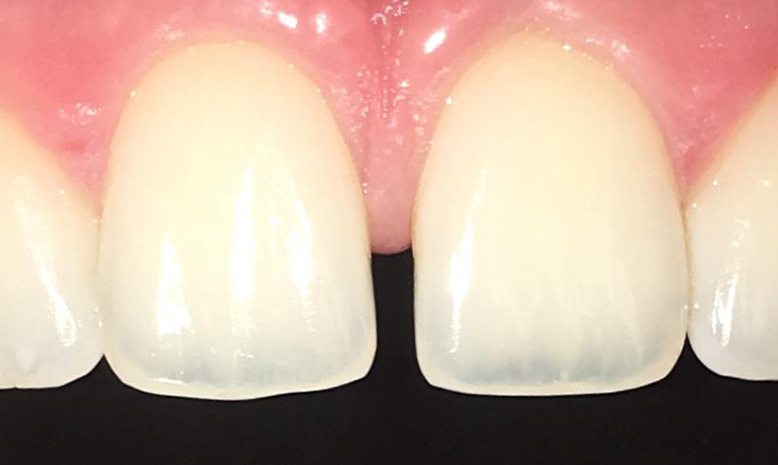

Composite (Aesthetic) bonding

Composite Bonding involves the application of a tooth coloured resin to fix the shape or colour of your tooth.

Composite bonding can easily repair chips, fractures, decay and discoloured teeth. Unlike porcelain veneers, which are manufactured in a laboratory and require your dentist to remove a large amount of healthy tooth structure, composites can be applied in a single office visit with minimal tooth removal.

- Very natural in appearance